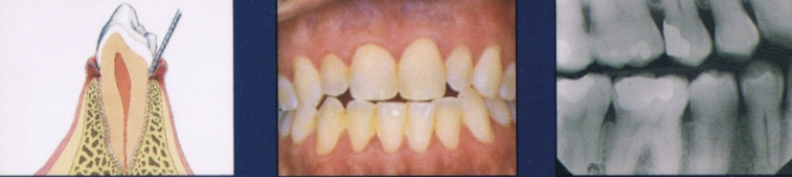

Describe gingivitis

Inflammation of the gingiva

Clinically: change in color, gingival form, position, surface appearance, presence of bleeding/exudate

Describe early stage of periodontitis

Progression of gingival inflammation into deeper periodontal structures and alveolar bone crest

Slight bone loss

Slight loss of CT attachment + alveolar bone